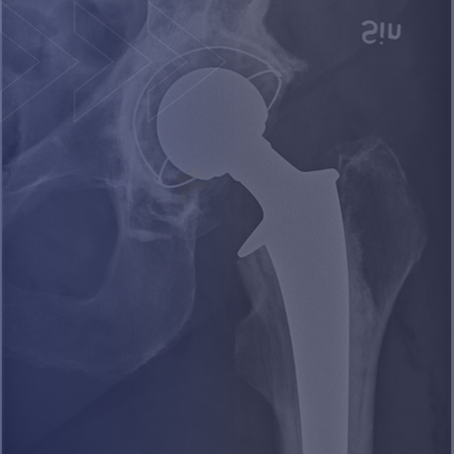

Resources for Hip and Knee Recovery